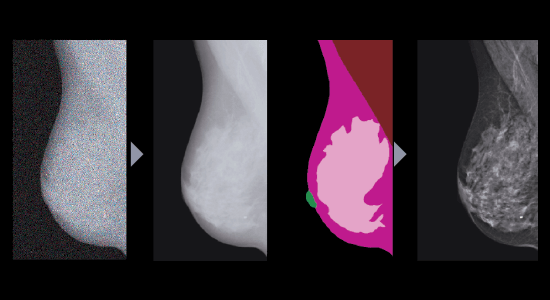

TRUVIEW® M2: Potente procesamiento de imágenes con IA con optimización del tipo de mama

- Aumento de la microcalcificación y la detectabilidad de lesiones con imagen de bajo ruido.

- Representación clara de las estructuras mamarias mantenidas para senos densos.

- Imágenes consistentes independientemente de la variación de la mama.

- Imágenes de alta calidad mantenidas a dosis bajas con tecnología de IAQ.

- Imágenes tridimensionales de alto contraste.